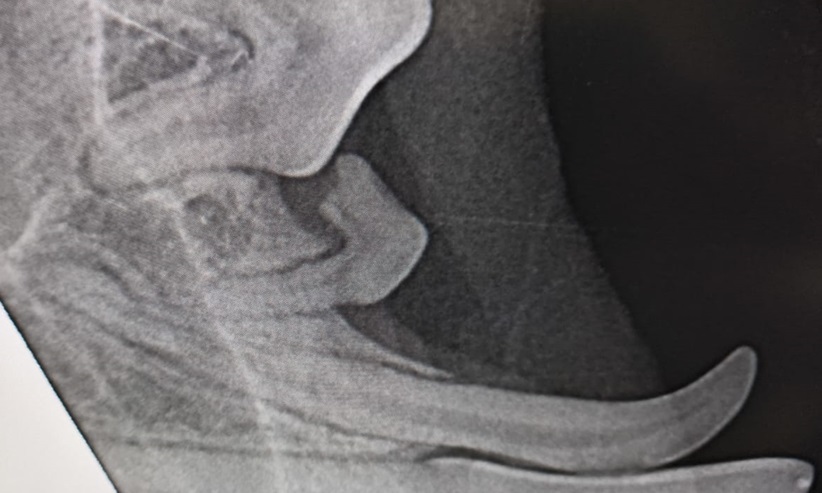

Diese Beispiel zeigt zugleich die Wichtigkeit intraoraler Röntgenaufnahmen vor jeder Zahnextraktion (in diesem Fall zwei Milchzähne, wovon einer zur Hälfte resorbiert ist).

Unsere Praxis verfügt über eine moderne Röntgenröhre, die es uns ermöglicht digitale intraorale Aufnahmen von den Zähnen der bei uns behandelten Patienten anzufertigen.

Wir verfügen über digitales (intraorales) Dentalröntgen und bieten ein breites Spektrum zahnmedizinischer Eingriffe an.